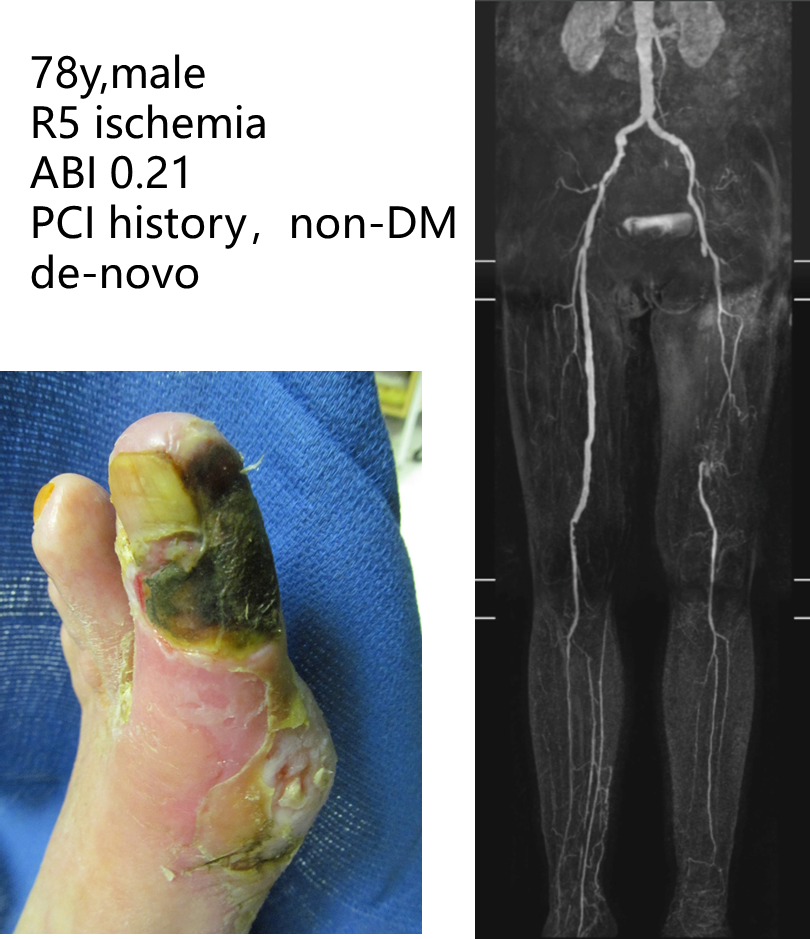

★ Case 1

技术失败:R5 ischemia → 股总-远端胫后In-situ GSV旁路

★ Case 2

4次EVTs反复复发:R5 ischemia → 腘P3-足背non-reversed GSV旁路

★ Case 3

EVT后临床失败:R5 ischemia → 腘P3-足底动脉 reversed GSV旁路

为什么需要更远端的旁路?

可以提供愈合伤口的充沛血流

The more distal, the more powerful